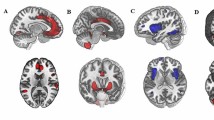

Higher anxiety-depression predicted lower FA in the tracts between the amygdala and key regions of the CON, DMN, and FPN. Specifically, greater symptoms relate to lower FA in the tracts between the amygdala and the dorsolateral PFC (dlPFC) within the FPN (β = -.12, t(440) = -3.11, corrected p = .01, R 2 = .30, f 2 = .43), the anterior PFC within the CON (β = -.09, t(439) = -2.28, corrected p = .05, R 2 = .30, f 2 = .43), and the parahippocampal gyrus (PHG) within the DMN (β = -.10, t(467) = -2.62, corrected p < .03, R 2 = .41, f 2 = .69) (Table 3). Figure 1 (left pane) provides a visual representation of the tracts between the amygdala and PFC.

The connection probability analyses also suggested that there was a negative influence of anxiety-depression on the connections between the amygdala and FPN. However, in this case the amygdala – inferior parietal lobe (IPL) tract showed a negative relationship with increasing symptoms (β = -.10, t(445) = -2.11, corrected p = .05, R 2 = .13, f 2 = .15; Table 4). Furthermore, anxiety-depression also predicted the connection probability of the amygdala and the temporal-parietal junction (TPJ) of the VAN (β = -.09, t(443) = -2.03, corrected p = .05, R 2 = .15, f 2 = .18; Table 4). Interestingly however, these two tracts appear to share a lot of voxels (Fig. 1, right pane).

Greater symptoms of anxiety and depression were negatively associated with tract volume in the amygdala – dlPFC tract of the FPN (β = -.10, t(439) = -2.14, corrected p = .05, R 2 = .17, f 2 = .20; Fig. 1; Table 5). No other effects were significant.